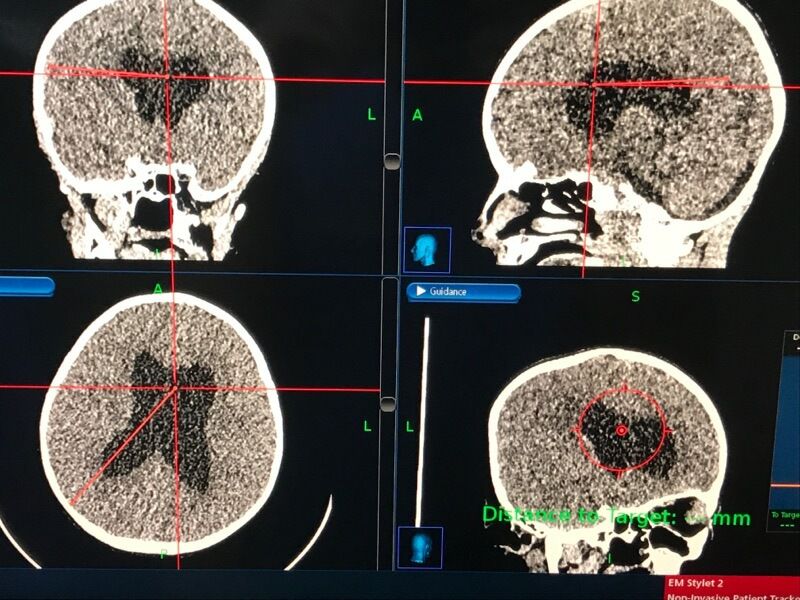

(1)立体定向下右顶叶新月形皮肤切口;

(4)立体定向规划的近端导管径路进入侧脑室房部,避开脑沟/血管;

(5)该径路止于近额角处,以降低侧脑室房部脉络球进入分流器造成分流器故障风险。

使用立体定向计划和导航系统,沿设定轨迹将导管送至靶位置。